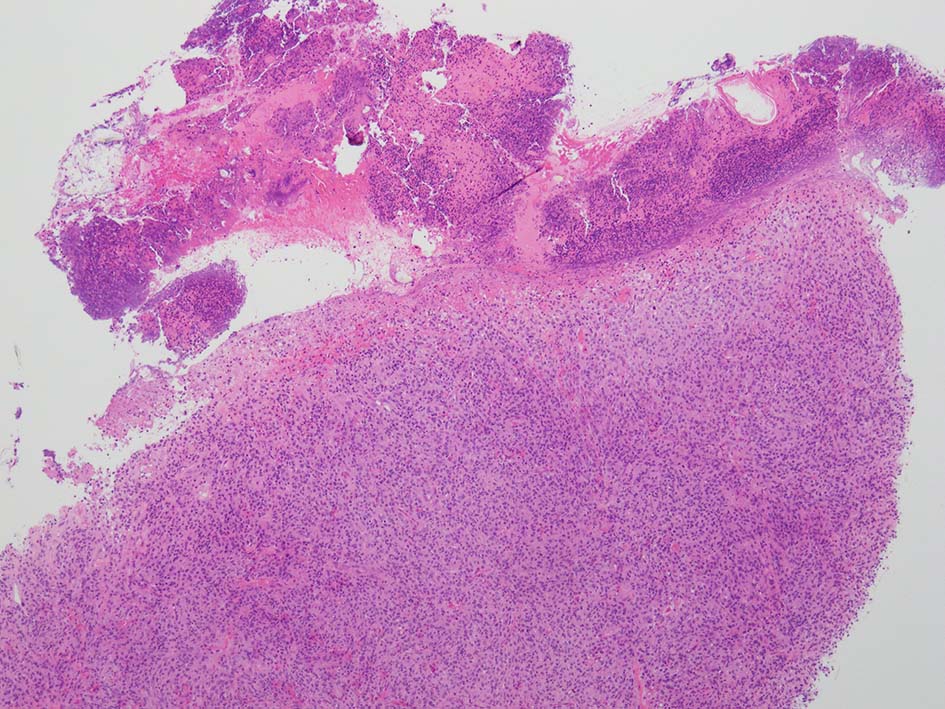

loupe像:表面に痂皮形成. 均等な組織像で,壊死や出血はみられない. 低倍ではspindle cellの密な増殖があるように見える. 拡大所見では, 類円形, 卵円形, ねじれた桿状の核, くびれ,勾玉様の核など不整形な核をもつ細胞が増殖している. クロマチンは繊細な傾向で, 核小体を1個もつ核が認められる. 高倍率10視野で 1-2個の核分裂像が数えられた.

樹状細胞性腫瘍, 組織球性腫瘍, histiocytic sarcoma(あまり異型がめだたない)などを考えて鑑別, 免疫染色をおこなった.

CD20, PAX5, CD3, CD5 リンパ球マーカは陰性. Dendritic cell marker (CD1a, CD123, Langerin, etc)は陰性. S-100, CD168, CD68(KP-1)が陽性. 組織球増殖病変と考えられた. foamy macrophageやgiant cellsはほとんど認められない. 高異型度, 多型細胞の出現はないが, MIB-1 LIが高く, mitosisも増加している, 悪性の心配あり, 治療方針の決定のため consultationを行った.

2か月ほどの間に隆起した亜急性病変で, 下記 Juvenile xanthogranulomaの早期病変にあたるのかもしれない, (管理人)

大学病院に紹介され摘出手術がおこなわれた. 手術検体でも非典型的ではあるものの juvenile xanthogranuloma に矛盾しなかった。

手術検体でも、明瞭な泡沫細胞は指摘できませんでしたが、Tuton型巨細胞が少数確認できた. 免疫染色の結果も、juvenile xanthogranuloma を支持する所見であった。 全身精査を行ったところ、他に病変は見当たらず、単発性であることが確認できた。(大学病理診断担当先生からの報告)